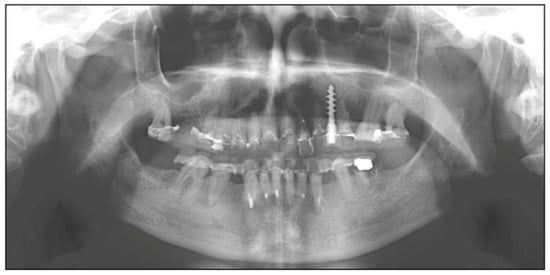

2. Case Report